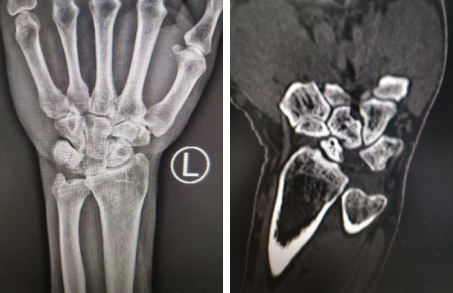

家住安徽省宿州市濉溪县的孙先生,5年前因一次意外摔倒左腕受伤后一直感到左腕疼痛,也多次前往当地医院进行就诊,一直没有发现疼痛的原因,2020年11月9号他在亲戚的介绍下来到了必威官方首页官网betway。必威官方首页官网betway手外科朱辉主任为其查体后诊断为:月骨脱位。

据朱辉主任介绍:月骨脱位损伤常容易漏诊,很多医生因为不是专业的手外科医生,对这种临床表现认识不足,对X线认识不足,早期很少能做出诊断,绝大多数在后期因腕关节疼痛、活动受限就诊而被发现。早期暴力挤压后可使月骨向掌侧脱位,对月骨的血供造成影响,早期发现及时处理后可恢复月骨血运,预后较好,但是由于孙先生受伤时间较长,月骨已经坏死,只能手术剔除月骨,并将头舟关节融合,从而支撑起腕骨。